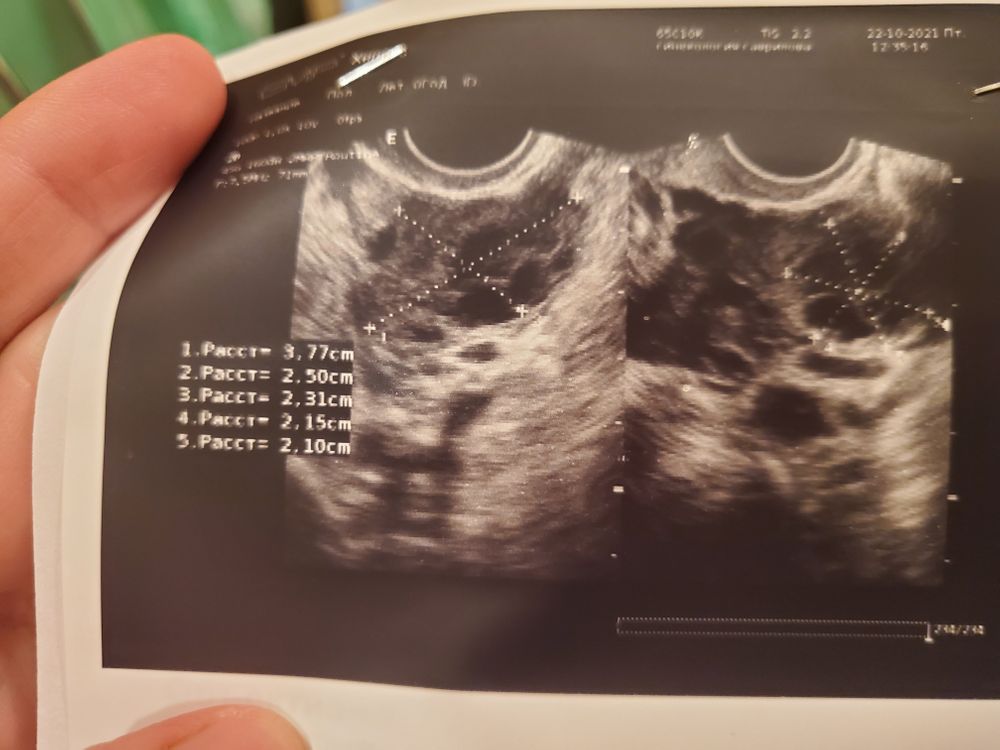

Девочки, кто понимает, это яичники с фолликулами внутри?

на фото яичники с фолликулами, да)